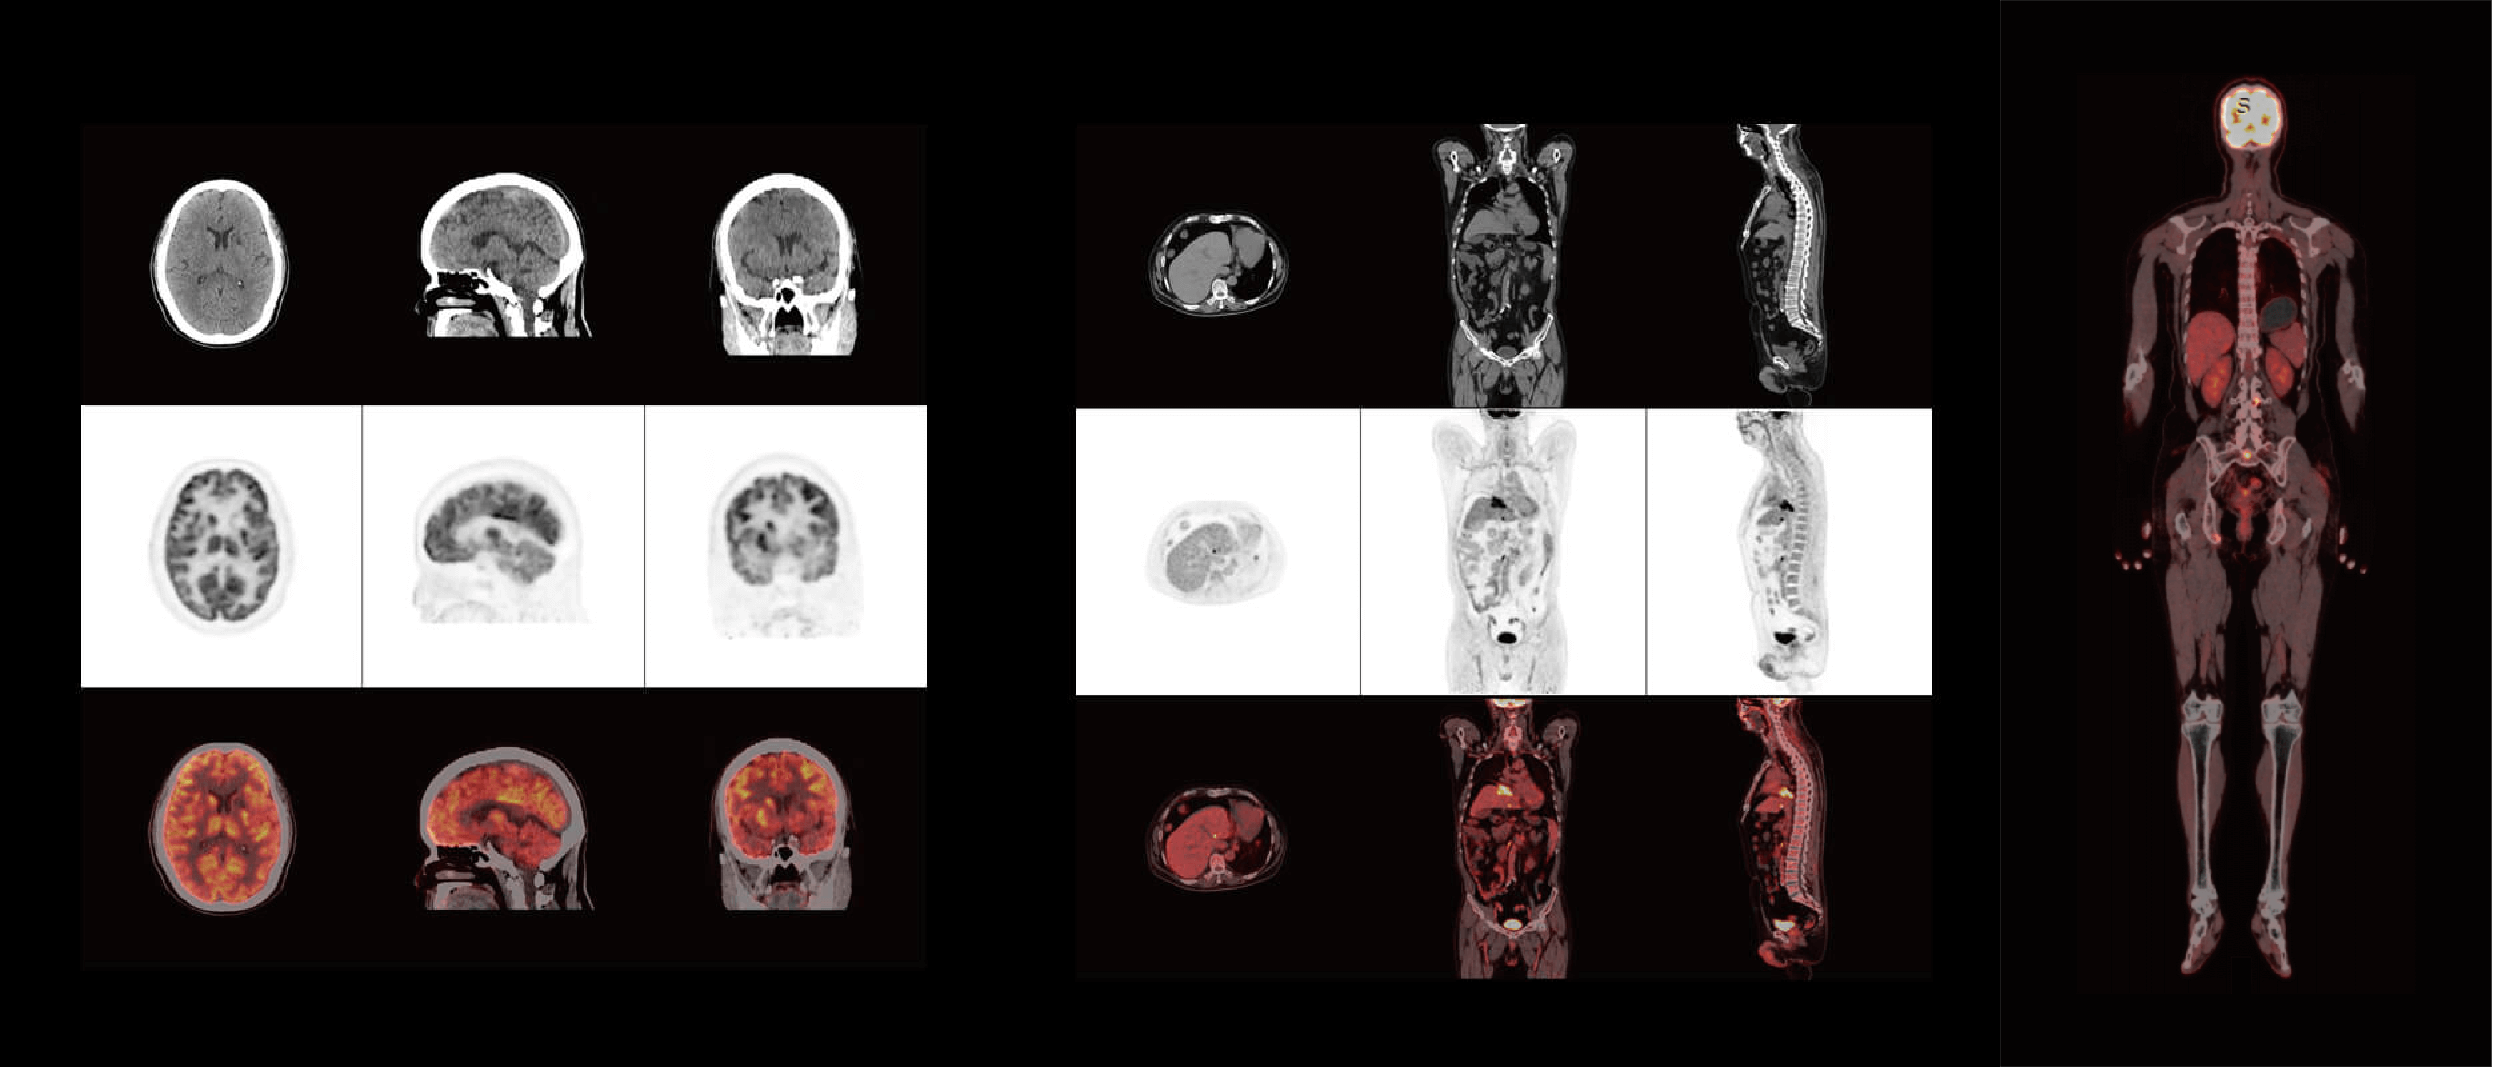

ScintCare PET/CT 730T

概述

MF 數(shù)字化探測器

SiPM 和 LYSO 晶體 1:1耦合先進(jìn)設(shè)計

超大軸向視野

302mm 軸向視野,1mm 級別高精度高清精準(zhǔn)顯像

運動偽影校正功能

自由呼吸運動,頭部運動偽影校正,臨床信噪比更優(yōu),圖像更真實

高性能“智能天成 天域 CT”

128 層全能 CT,搭載 2048x2048 重建矩陣,助力 CT 高清顯像

高效智能處理平臺

BrainPower智能引擎和 DosePower 低劑量平臺